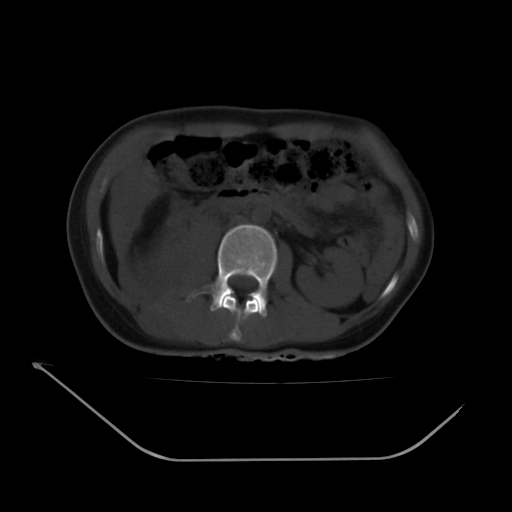

以下是引用liuyue在2008-7-19 13:02:00的发言:[br]1.肝右叶后下段及右肾挫裂伤伴腹腔积血。[br]2.右侧多发性肋骨骨折、横突骨折、右髂骨骨折伴周围软组织挫伤。[br]3.右侧腰大肌肿胀,并可见低密度影,如为气体,则肠道挫裂伤待除外。

以下是引用zhengfaming在2008-7-19 14:42:00的发言:[br]1.肝右叶后下段及右肾挫裂伤伴腹腔积血。脾脏挫裂伤待排[br]2.右侧多发性肋骨骨折、横突骨折、右髂骨骨折伴周围软组织挫伤。[br]3.右侧腰大肌肿胀,并可见低密度影,如为气体,则肠道挫裂伤待除外